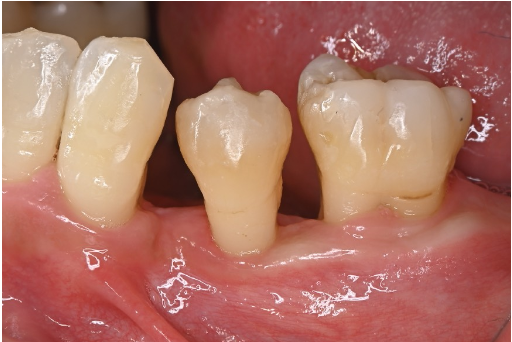

症例3

| 患者様データ | 40代 男性 |

| 来院時の主訴 | 「歯がグラグラする。」 |

| 医院の診断 | 重度の歯周病 |

| 通院期間 |

1年半 |

| 来院回数 | 20回 |

| 治療費 | 総額:240,000円(税抜)+歯周基本治療は保険適用診療 【内訳】 保険適用診療:歯周病検査・歯磨きや生活習慣指導・歯石取りクリーニング 自由診療:歯周組織再生療法240,000円(費用は範囲によって異なります。) |

| リスクと副作用 | 定期的なメインテナンスが必要、正しい歯磨き習慣・生活習慣が必要不可欠 |

| ここがこだわりのポイント!☝ | 少しチャレンジングは症例ではありますが、歯周病によって無くなってしまった歯周組織(歯根膜・セメント質・骨・歯肉)が手術により改善しました。 |